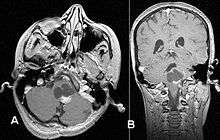

Usually—depending on the interview of the patient and after a clinical exam which includes a neurological exam, and an ophthalmological exam—a CT scan and or MRI scan will be performed. A special dye may be injected into a vein before these scans to provide contrast and make tumors easier to identify. The neoplasm will be clearly visible.

If a tumor is found, it will be necessary for a neurosurgeon to perform a biopsy of it. This simply involves the removal of a small amount of tumorous tissue, which is then sent to a (neuro)pathologist for examination and staging.[7] The biopsy may take place before surgical removal of the tumor or the sample may be taken during surgery.

Visual aspect

Macroscopically, an astrocytoma is a mass that looks well-circumscribed and has a large cyst. The neoplasm may also be solid.

Under the microscope, the tumor is seen to be composed of bipolar cells with long "hairlike" GFAP-positive processes, giving the designation "pilocytic" (that is, made up of cells that look like fibers when viewed under a microscope[8]). Some pilocytic astrocytomas may be more fibrillary and dense in composition. There is often presence of Rosenthal fibers,[9] eosinophilic granular bodies and microcysts. Myxoid foci and oligodendroglioma-like cells may also be present, though non-specific. Long-standing lesions may show hemosiderin-laden macrophages and calcifications.